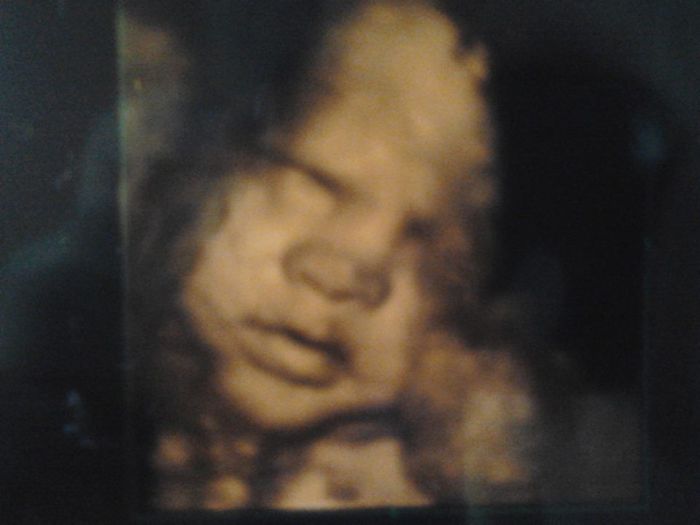

tak jsme dnes přišli z dnešní kontroly a já jsem si přinesla 3D obrázek. Hned se jdu pochlubit s naším slůňátkem Martínkem

. U nás chladno a prší !!! Huráááá !!!! Nevadilo by mi takové počsí už dokonce září. Zítra dodám fotečky oblečků a bříška, co už tak dlouho slibuji.